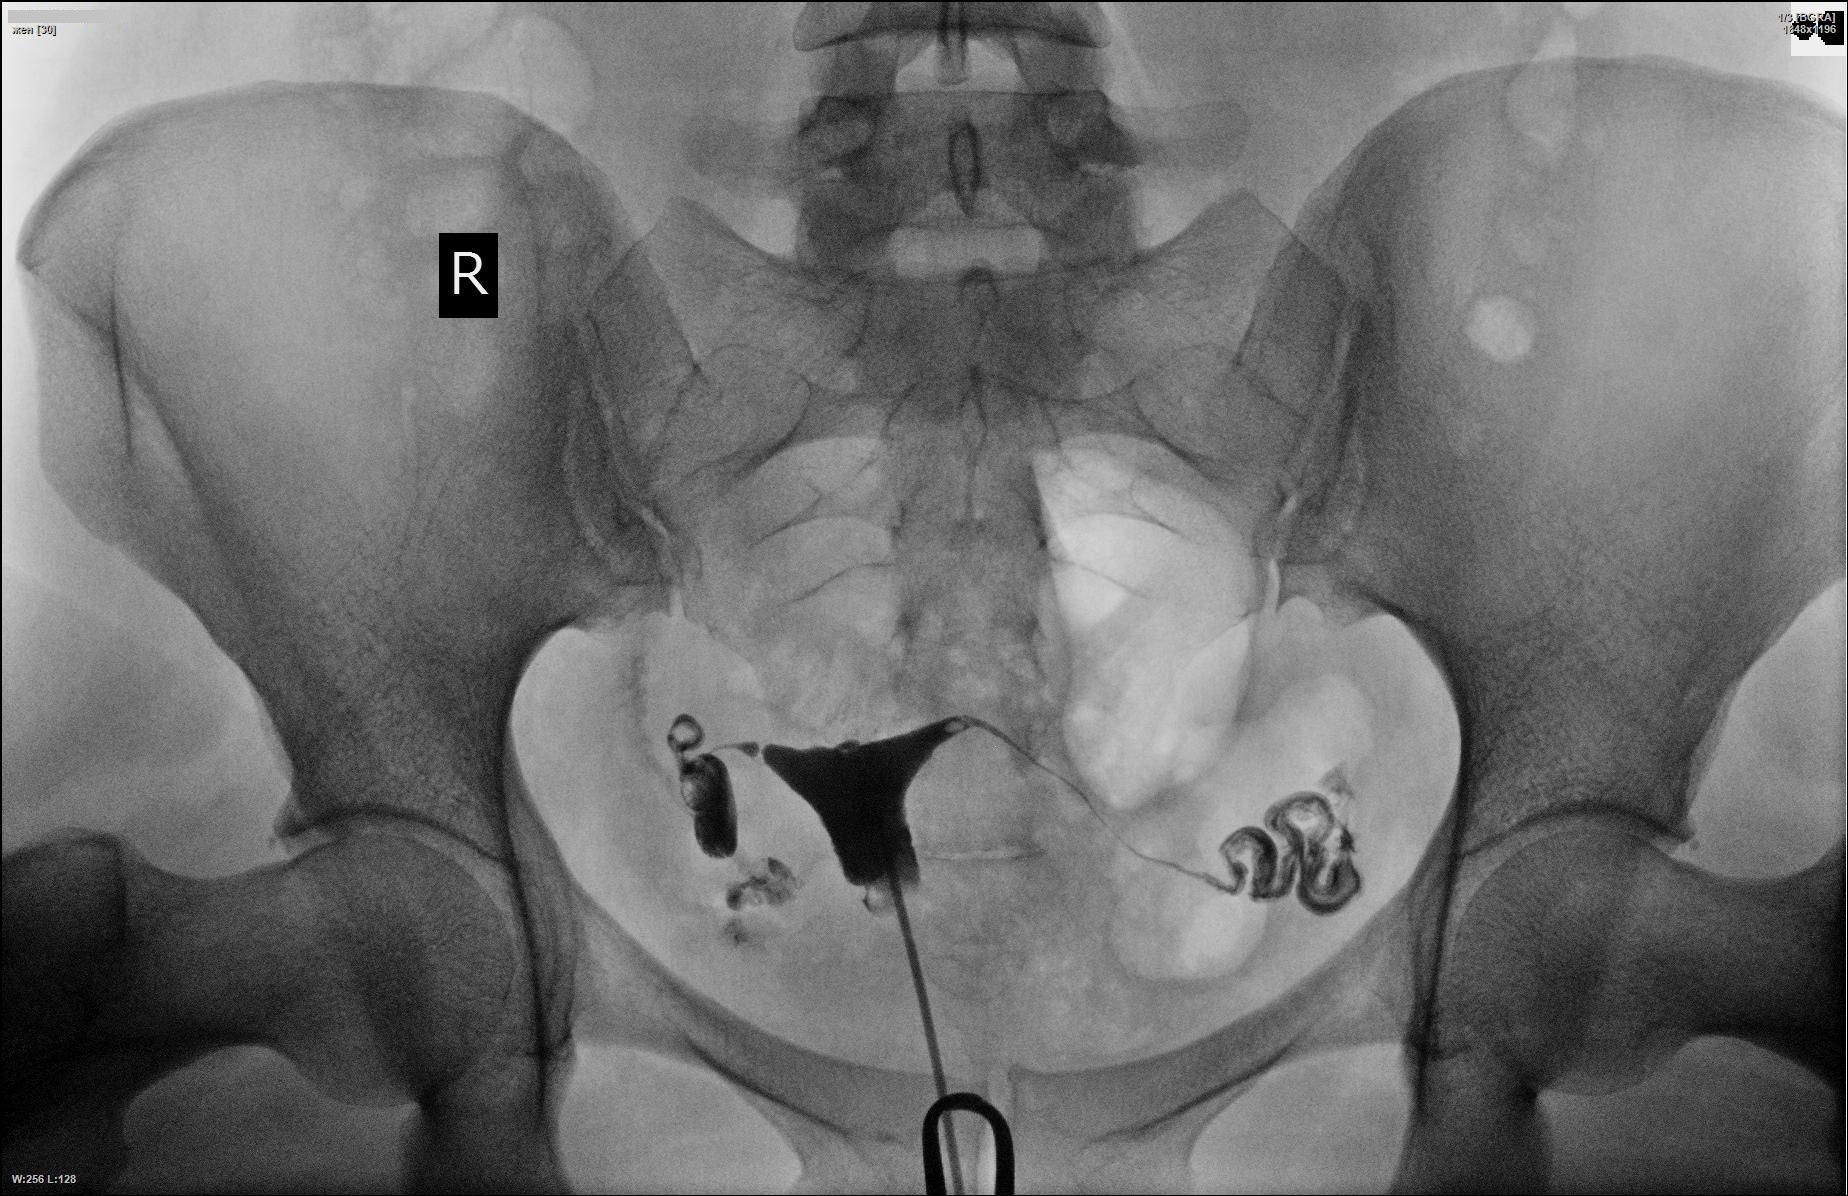

Гистеросальпингография: описание и фотографии